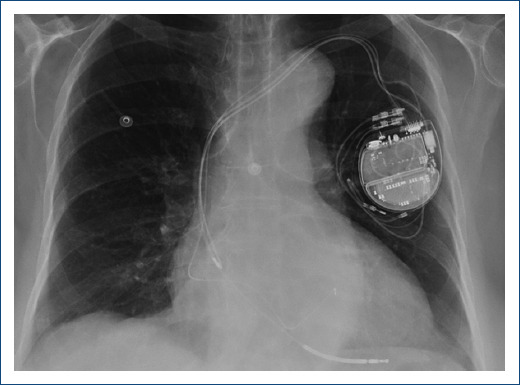

Due to the clinical suspicion of biventricular arrhythmogenic cardiomyopathy with sustained ventricular arrhythmias, cardioverter-defibrillator (ICD) implantation was decided. Subcutaneous approach, initially preferred due to persistent thrombus, was finally dismissed due to predicted high risk of inappropriate therapies in the screening test. Finally, a transvenous ICD was implanted with defibrillation electrode located in the posterior interventricular vein and left bundle branch pacing (Fig. 2) with a significant reduction of paced QRS duration (Fig. 3) and partial recovery of biventricular function during the follow-up. Subsequently, a genetic study was performed confirming a pathogenic variant in the DSG2 gene, which not only explained the phenotype but also allowed familiar cascade screening (Fig. 4).